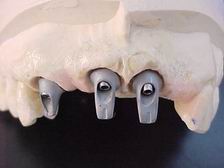

Munhões sobre réplicas dos implantes

Munhões personalizados

Munhões personalizados sobre modelo VISTA OCLUSAL